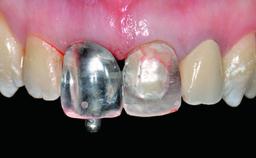

Replacement of a Failing Upper Left Central Incisor: Immediate Placement of an RC Bone Level Implant and Provisionalization

A healthy 23-year-old female patient was referred for a consultation on replacing tooth 21 with an implant-supported restoration. The patient had recently moved to the area and reported a history of endodontic and periodontal treatment for tooth 21. The tooth had been deemed non-restorable by her previous periodontist but since she was going to be moving, he recommended consulting to a dentist in her new city to continue her treatment. A review of her medical history yielded no significant findings and no known drug allergies. The analysis of her smile revealed a medium to high symmetrical smile line and a slightly discolored tooth 21.

Abutment Type CAD/CAM

Retention Cemented, with prosthesis margin < 3mm submucosal Cemented, with prosthesis margin < 3mm submucosal

Maxillomandibular Relationship Angle Class I and III

Mesio-Distal Space Symmetry +/- 1 mm of contra-lateral tooth

Provisional Implant-Supported Prosthesis Prosthodontic margin < 3 mm apical to mucosal margin Prosthodontic margin < 3 mm apical to mucosal margin